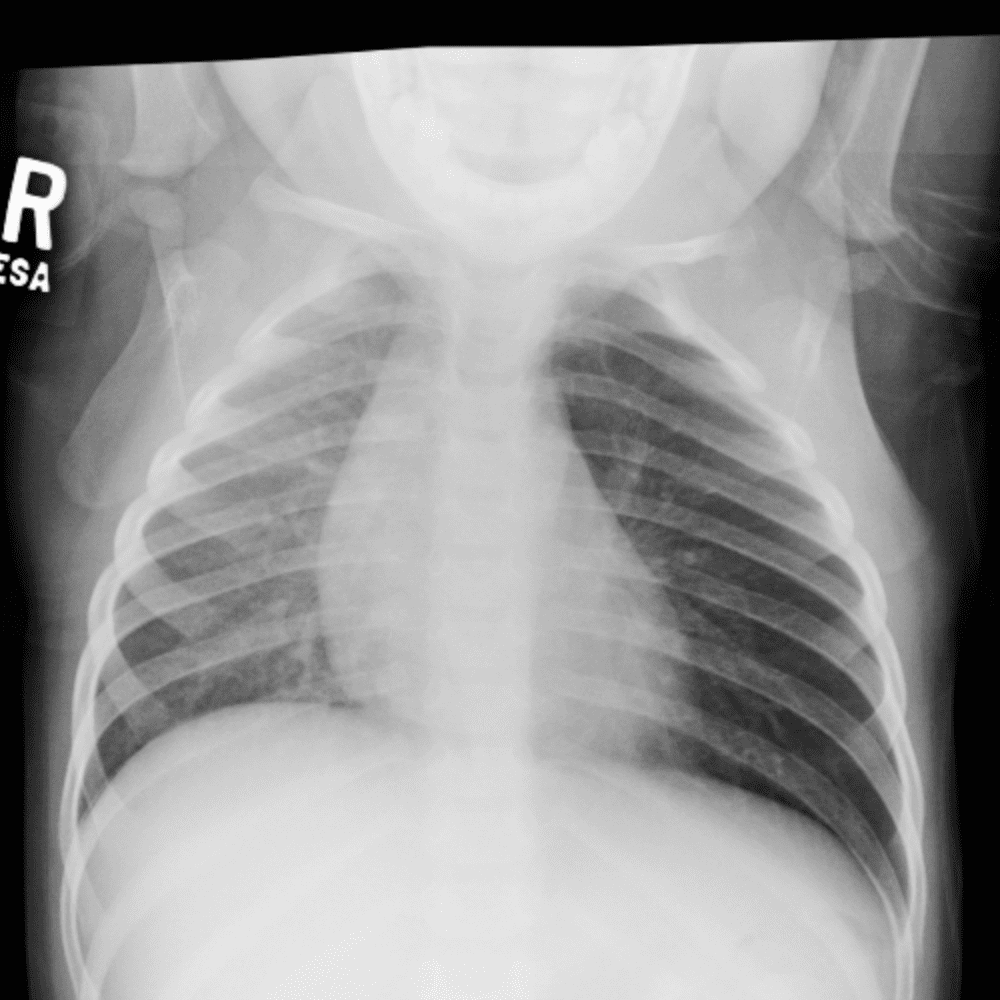

Peds Chest

Practice

Simulates call by including subtle or difficult cases and some normals.

50 cases